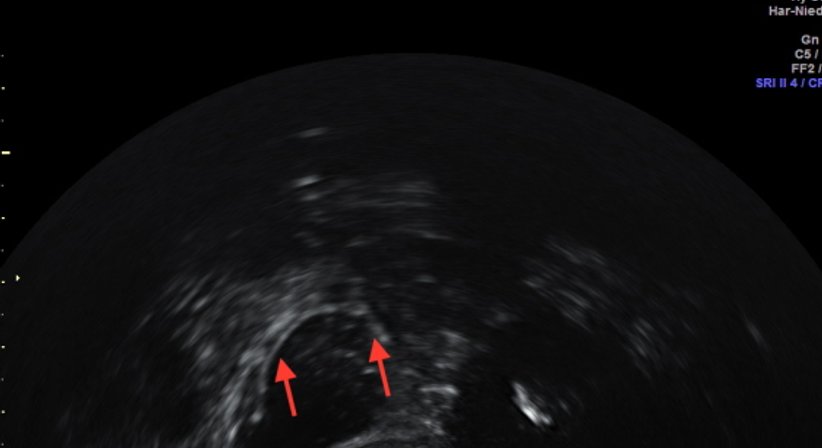

• HyCoSy – Tubendurchgängigkeitsprüfung ohne Strahlenbelastung mit 3D-Ultraschall.